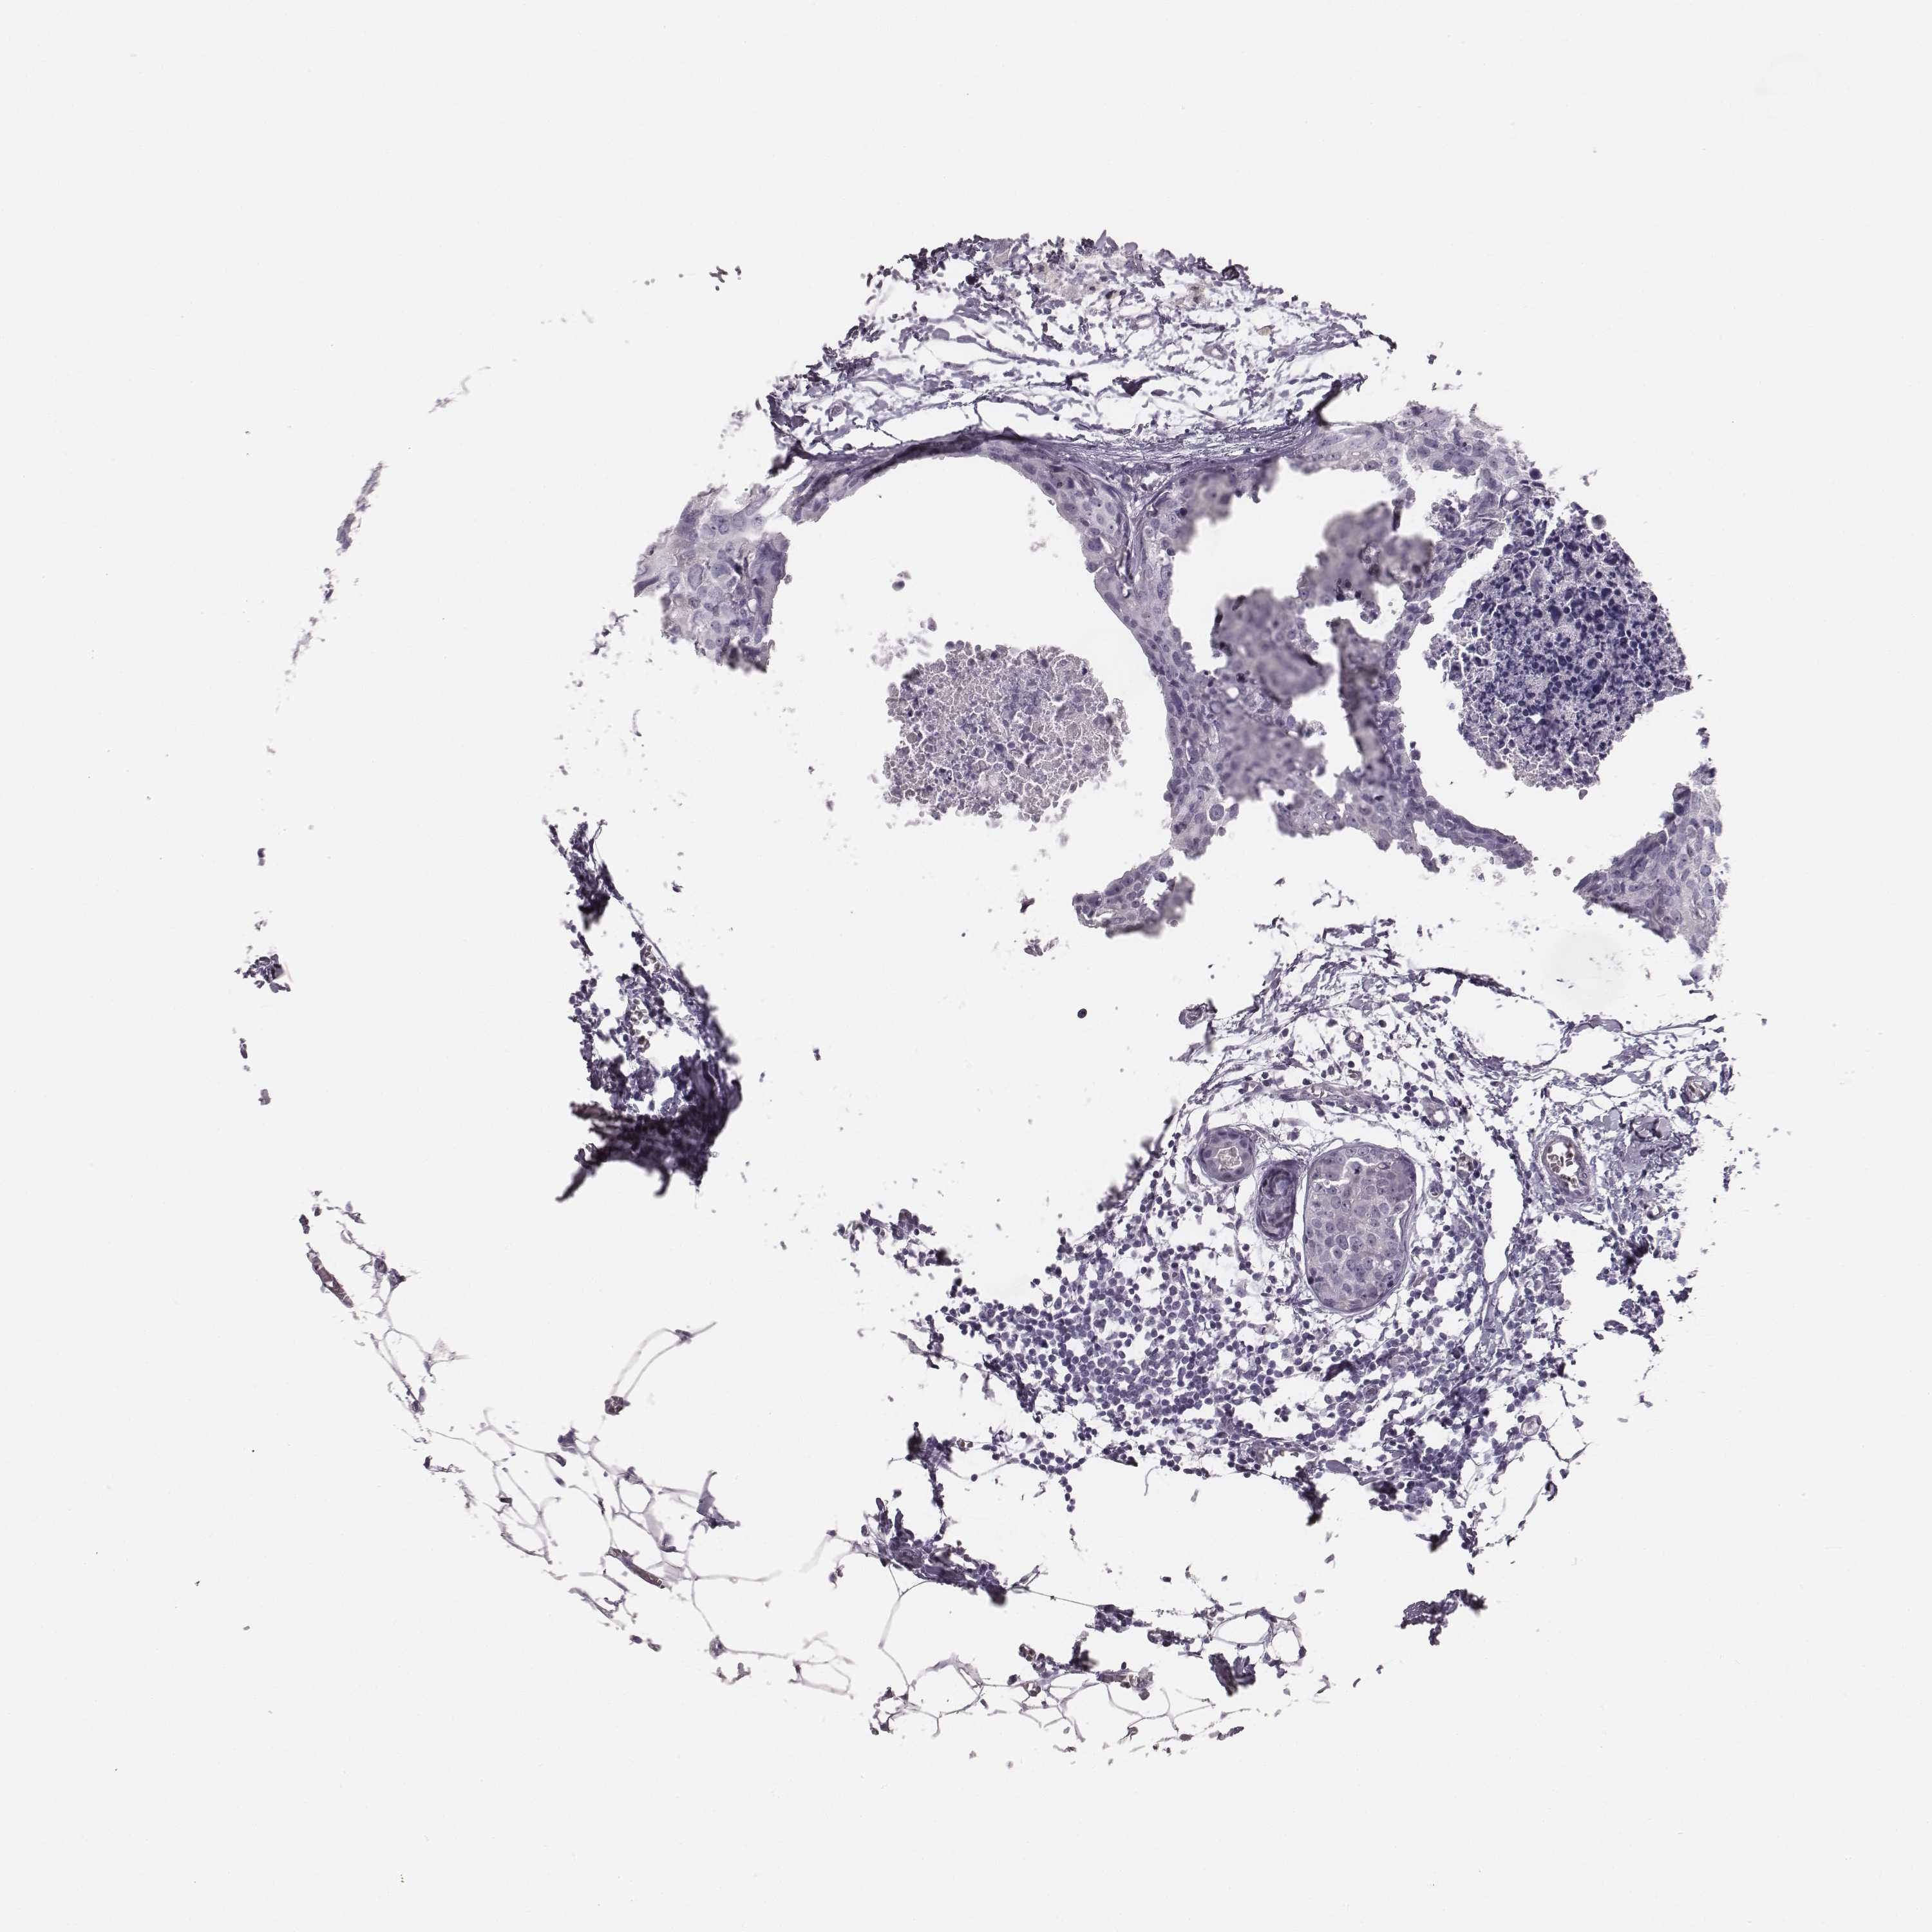

Breast cancer

Human cancer